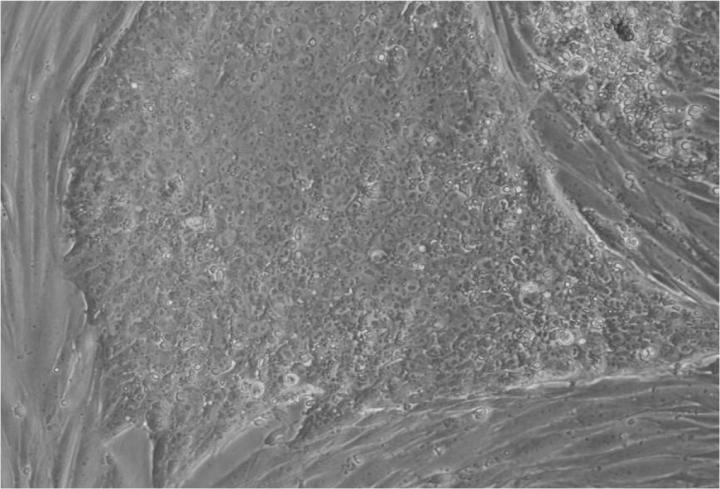

人類胚胎干細胞 (ESC) 是從囊胚(一種非常早期的人類胚胎)中發現的少量細胞產生的。從囊胚中取出的單個細胞生長成大量細胞以產生 ESC“系”。

胚胎干細胞研究的重點是干細胞系。這些是細胞群,都攜帶相同的基因,在實驗室中通過許多代細胞的許多生長和分裂周期生長。一個細胞系可以為許多研究人員提供大量細胞。

Jenny Nichols 拍攝的人類囊胚和人類胚胎干細胞圖像。愛丁堡大學 MRC 再生醫學中心向 SCNT 和多莉羊注射細胞核。